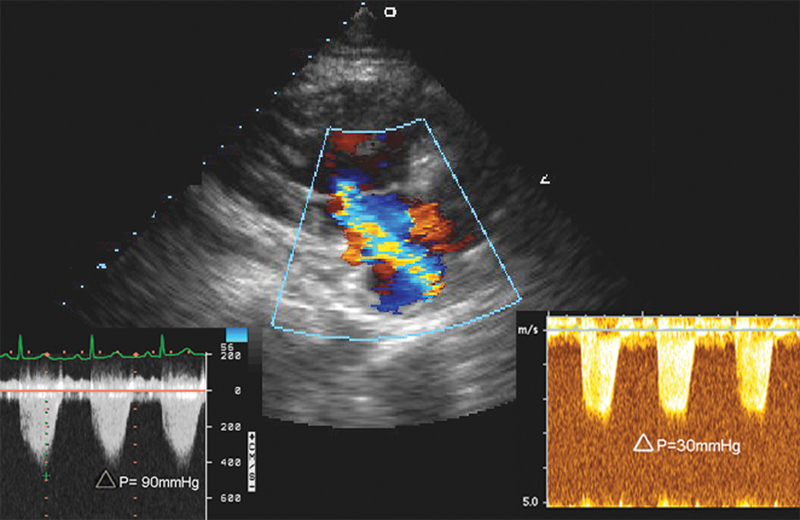

فحوصات تشخيصية لبعض امراض القلب والشرايين التاجية